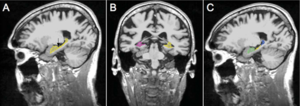

- 3.30 Intraoperative High-field Magnetic Resonance Imaging Combined with Functional Neuronavigation in Resection of Low-grade Temporal Lobe Tumors Involving Optic Radiation [Article in Chinese]

- 3.31 Fibrin-based 3D Matrices Induce Angiogenic Behavior of Adipose-derived Stem Cells